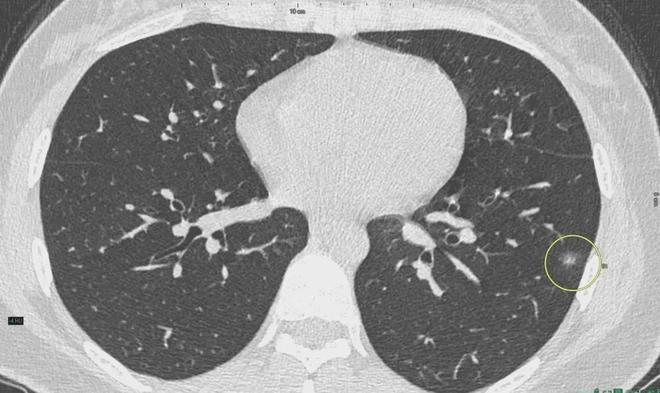

6、定期體檢:定期進行肺部檢查,及時發現并治療肺結節。

對于已經發現肺結節的患者,應及時就醫,進行進一步的檢查和治療,醫生會根據患者的具體情況制定個性化的治療方案,包括藥物治療、手術治療等,早期發現、早期治療是提高肺結節治愈率的關鍵。